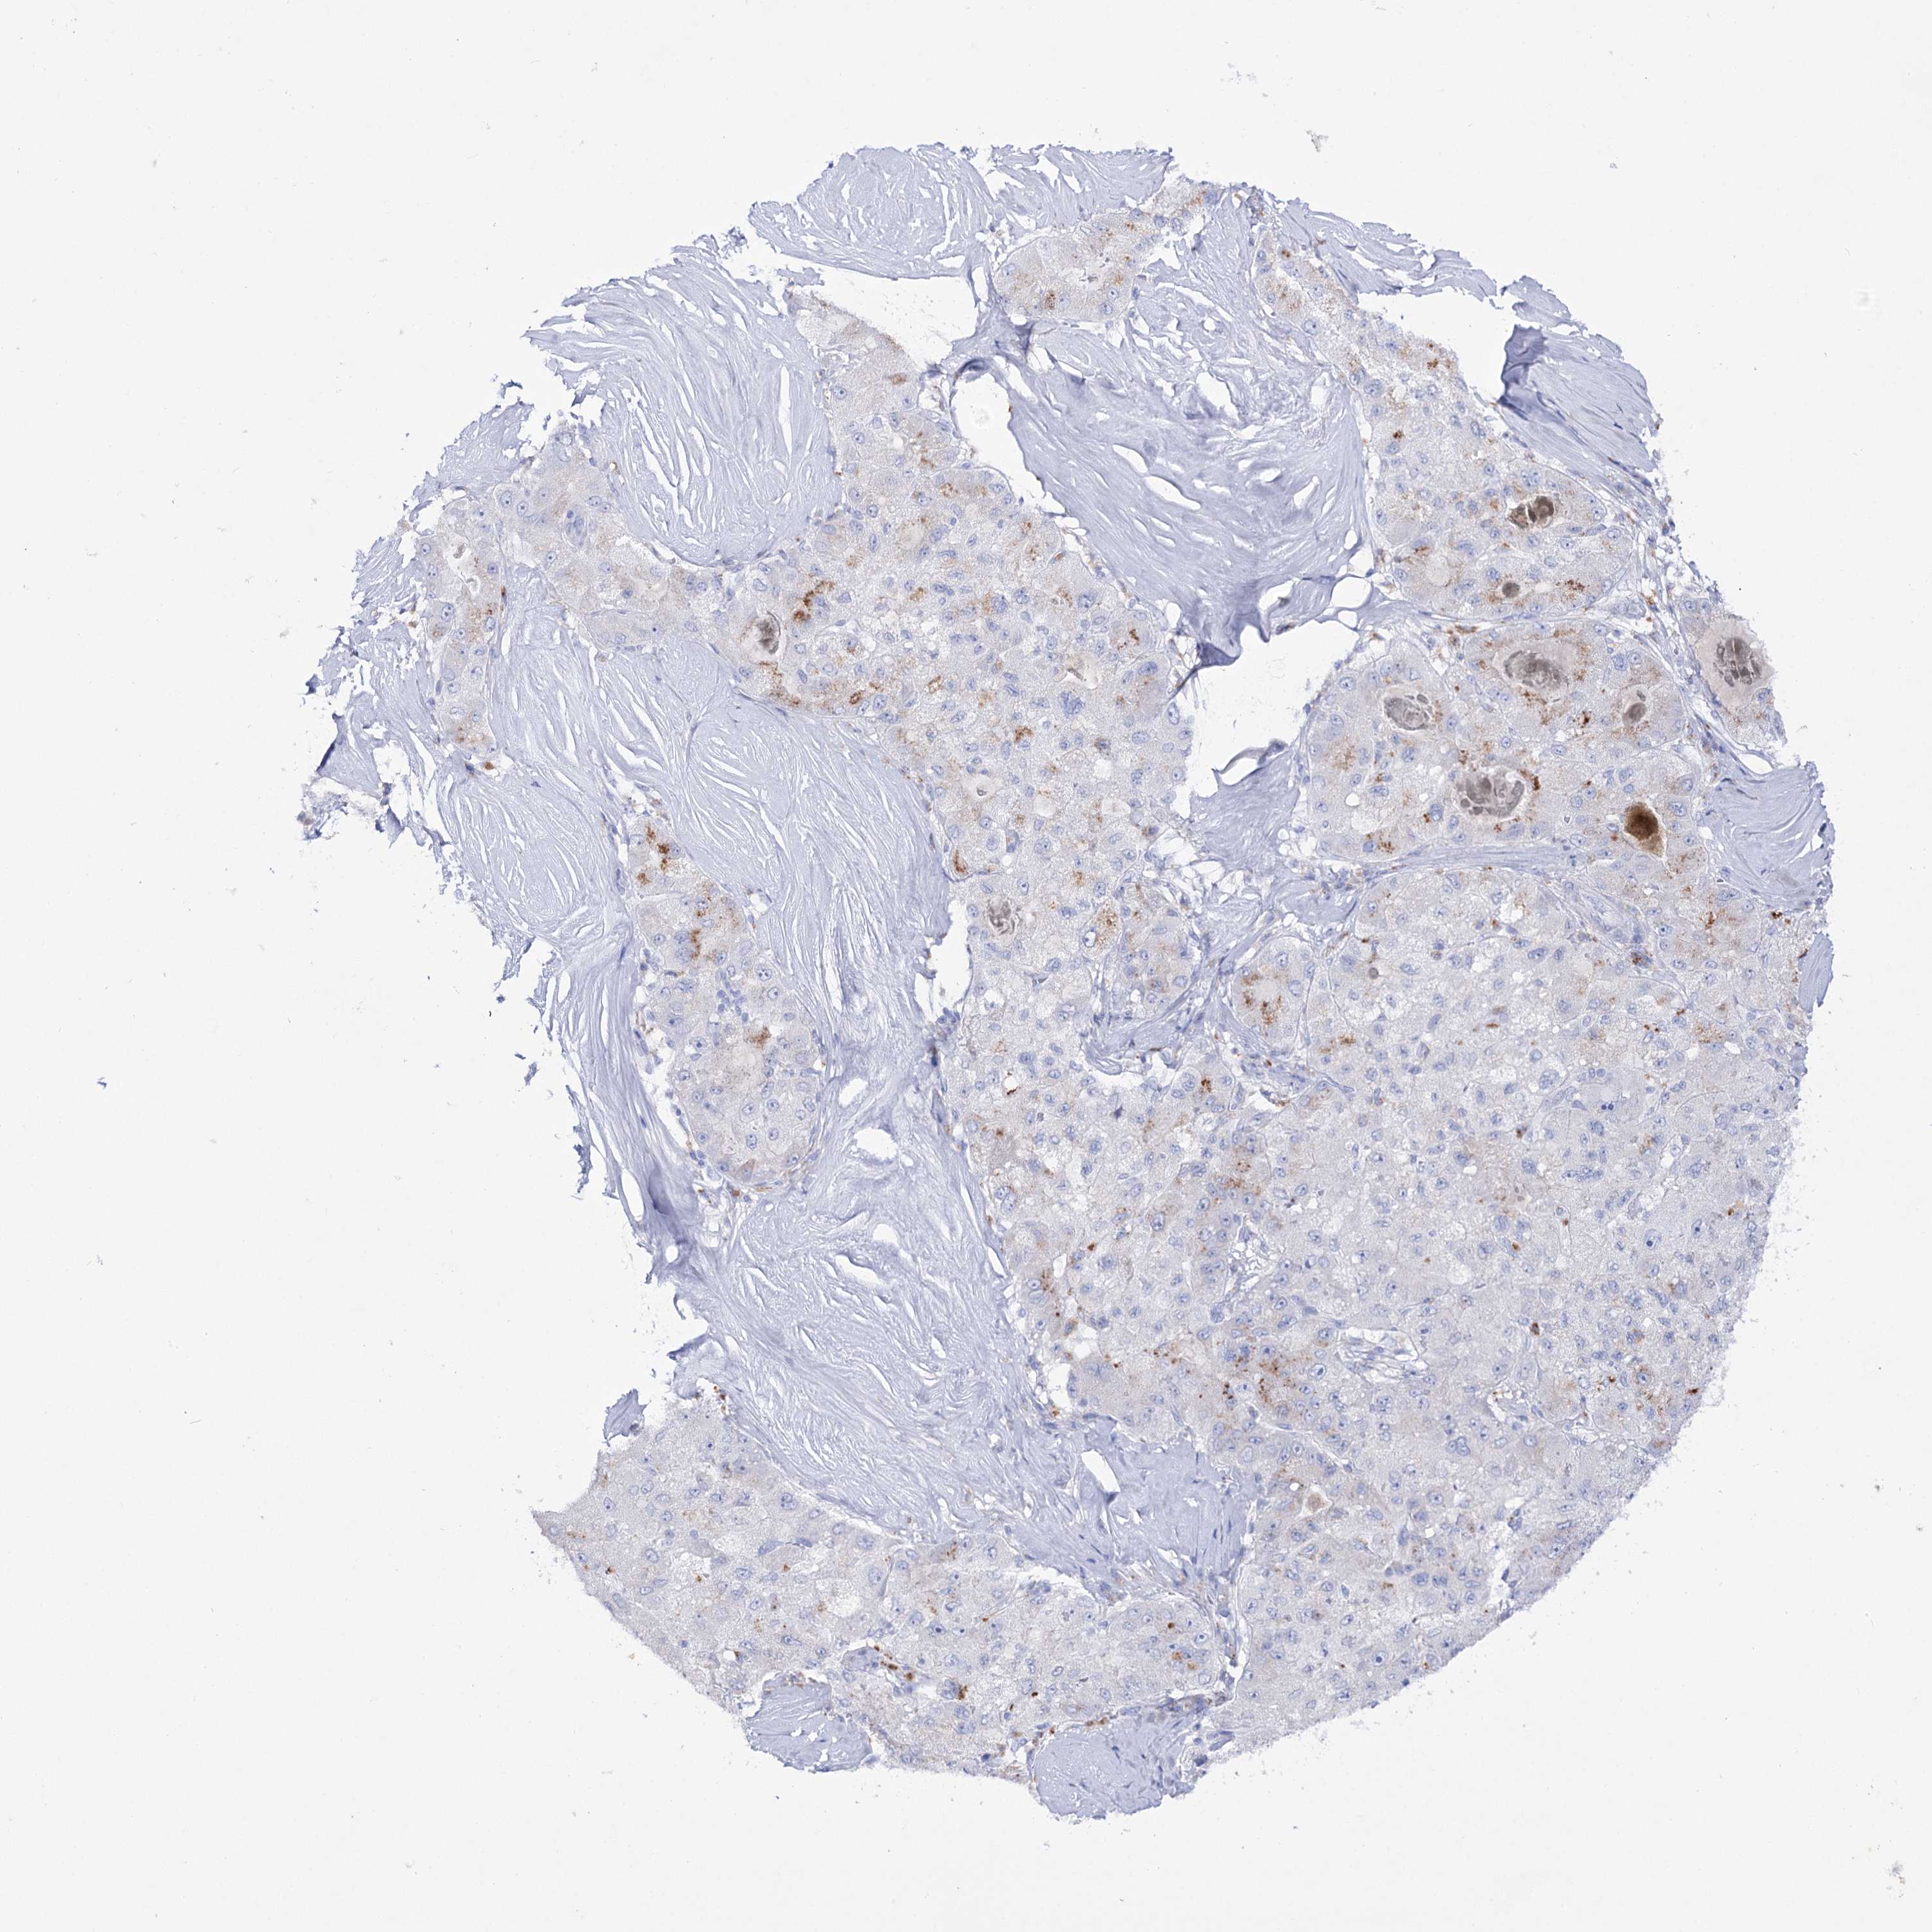

LIVER CANCER - Protein expressioni

A mouse-over function shows sample information and annotation data. Click on an image to view it in a full screen mode. Samples can be filtered based on level of antibody staining by selecting one or several of the following categories: high, medium, low and not detected. The assay and annotation is described here.

Note that samples used for immunohistochemistry by the Human Protein Atlas do not correspond to samples in the TCGA dataset.

Antibody stainingi

Antibody staining in the annotated cell types in the current human tissue is reported as not detected, low, medium, or high, based on conventional immunohistochemistry profiling in selected tissues. This score is based on the combination of the staining intensity and fraction of stained cells.

Each image is clickable and will lead to virtual microscopy that enables deeper exploration of all samples and also displays staining intensity scores, fraction scores and subcellular localization as well as patient and tissue information for each sample.

Antibody HPA038815

Staining

High

Medium

Low

Not detected

Intensity

Strong

Moderate

Weak

Negative

Quantity

>75%

75%-25%

<25%

None

Location

Nuclear

Cytoplasmic/membranous

Cytoplasmic/membranous,nuclear

Cholangiocarcinoma

Carcinoma, Hepatocellular, NOS